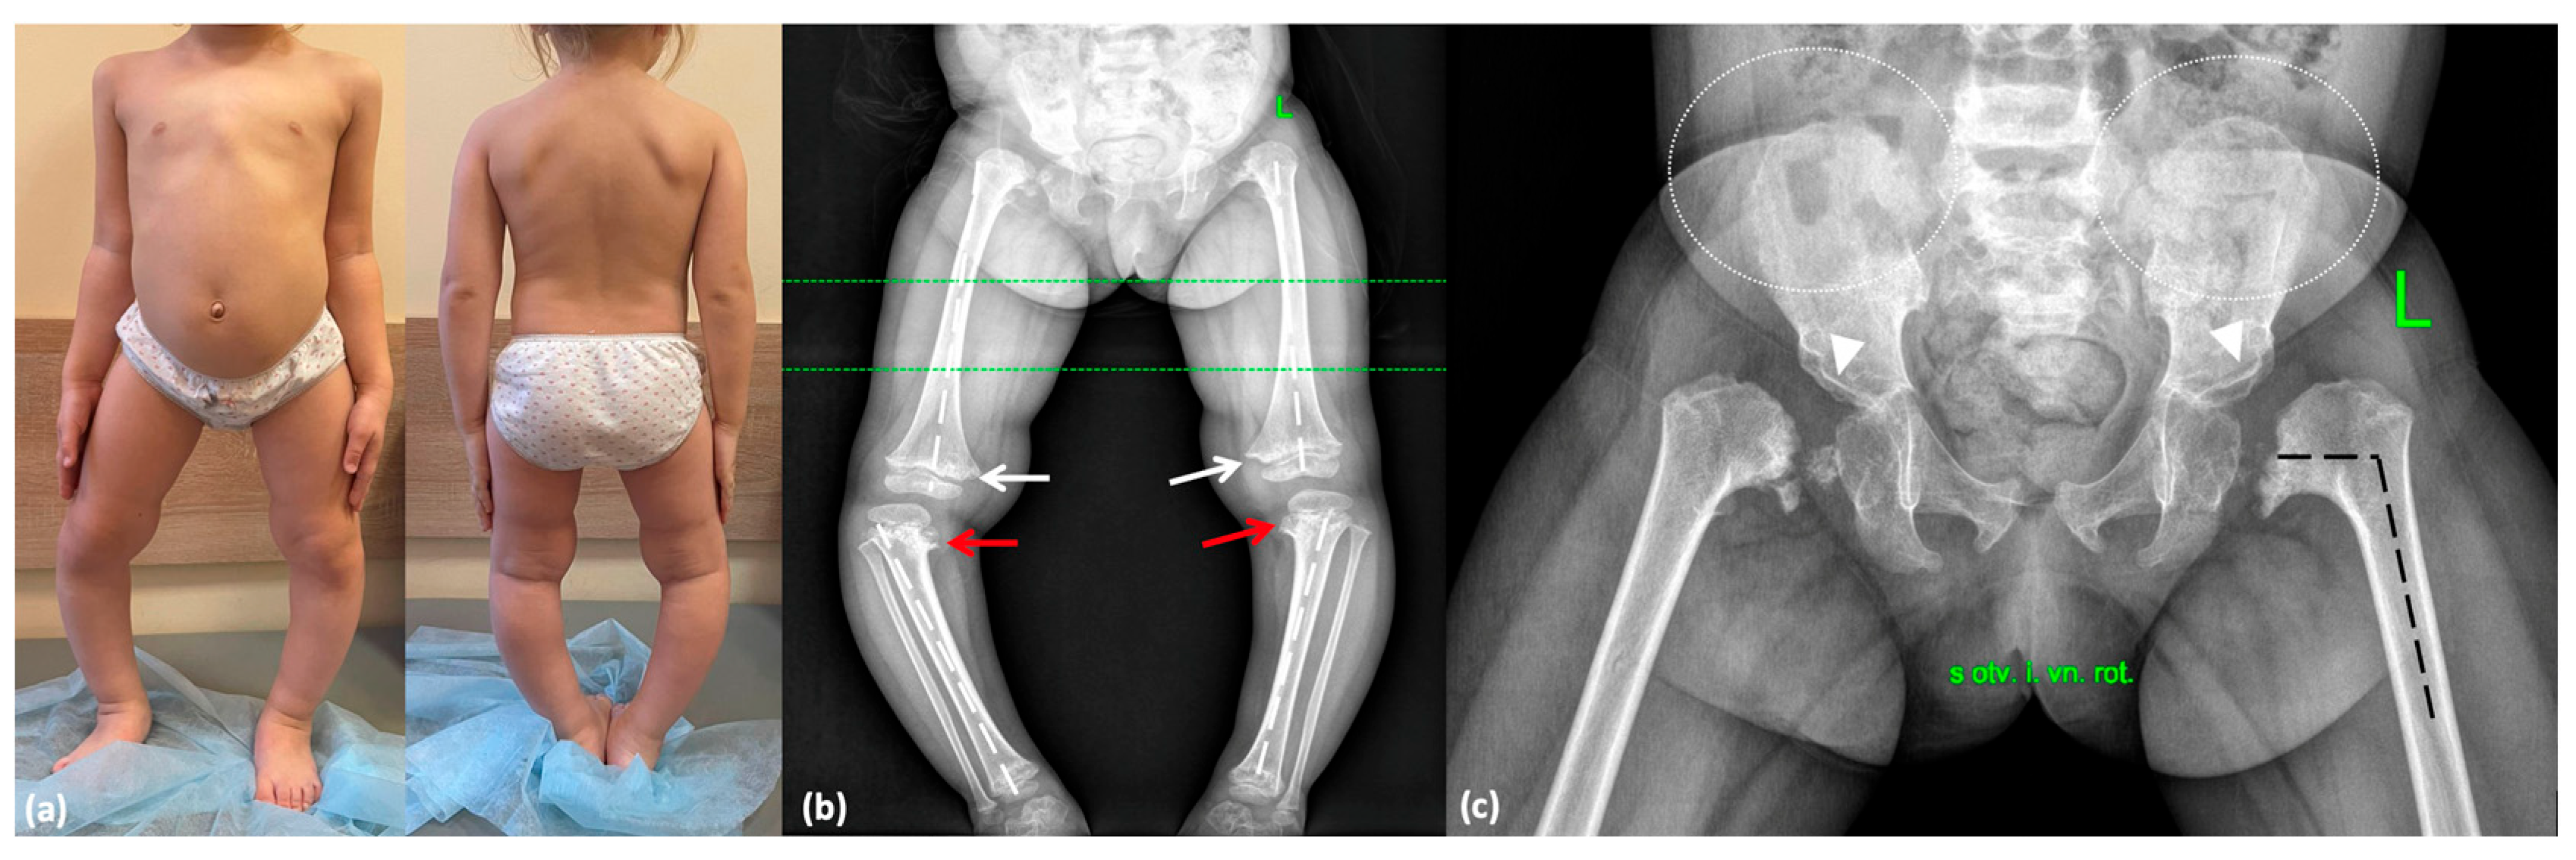

2.2.2. Family 2

| Referring diagnosis | Rickets-like disease, Blount disease, MED | Rickets-like disease, Blount disease, LCP disease, MED | LCP disease, MED | n/d | n/d |

| Irregular vertebral bodies | + | + | + | + | + |

| Metaphyseal involvement | + | + | + | + | + |

| Delayed epiphyseal ossification | + | + | n/d | + | + |

| Proximal femoral epiphyseal involvement | + | + | + | + | + |

| Coxa vara | + | + | + | + | + |

| Genu varum | + | + | − | +/− | − |

| Hyperlaxity | + | + | − | n/d | − |

| Others | Equino-abducto-plano-valgus foot deformity, cervicothoracic kyphosis | Varus deviation of the right foot | − | Pectus carinatum (mild) | Mild pectus excavatum, thoracic kyphosis |

| Orthopedic surgery | Hemiepiphysiodesis | Hemiepiphysiodesis | − | No but planned for future | n/d |